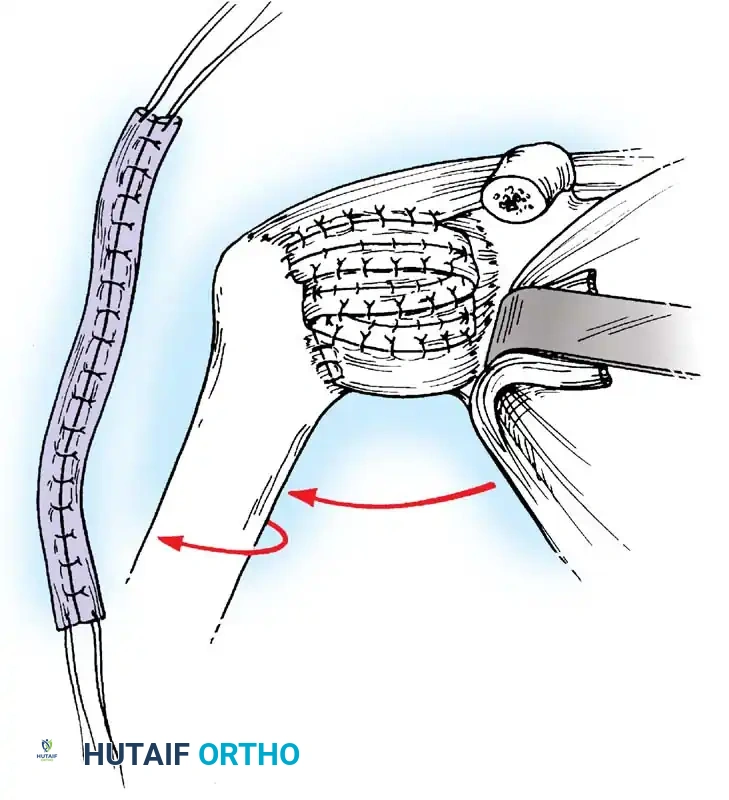

Capsular Shift and Closure

To address capsular redundancy, an inferior capsular shift is performed.

- The arm is positioned in 30 to 45 degrees of abduction and 20 degrees of external rotation.

- The inferior capsular flap is advanced superiorly and laterally, tensioning the IGHL complex. The sutures from the anchors are passed through the shifted capsule and tied.

- The superior flap is then brought down over the inferior flap in a "pants-over-vest" fashion to reinforce the anterior wall and close the rotator interval.

- The subscapularis split is loosely approximated with absorbable sutures. The deltopectoral interval is closed over a suction drain (if necessary), followed by routine subcutaneous and skin closure.